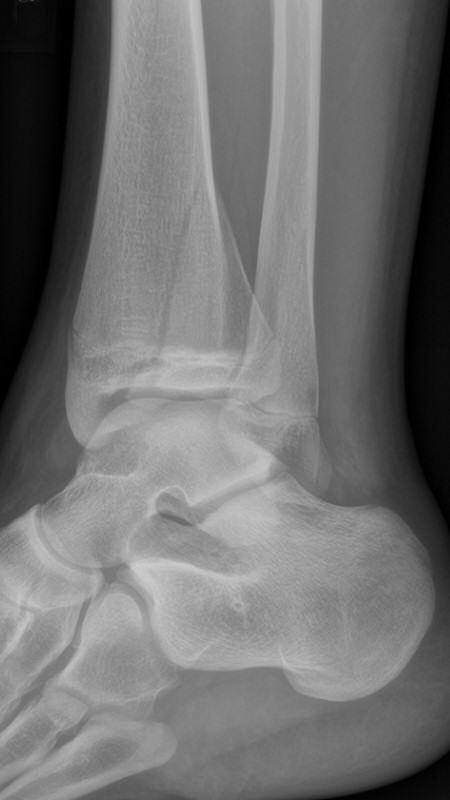

Distal tibiafyseolys SH 4 triplansfraktur (barn)

Triplanfraktur = triplansfraktur = treplansfraktur: fraktur i distala tibia som engagerar både metafys, fys och epifys. Kan vara 2, 3 eller 4 fragment. I 50 % av fallen är även fibula frakturerad [3].

Exempel på triplansfraktur hos nästan färdigvuxet barn

Efter operation med skruvfixation